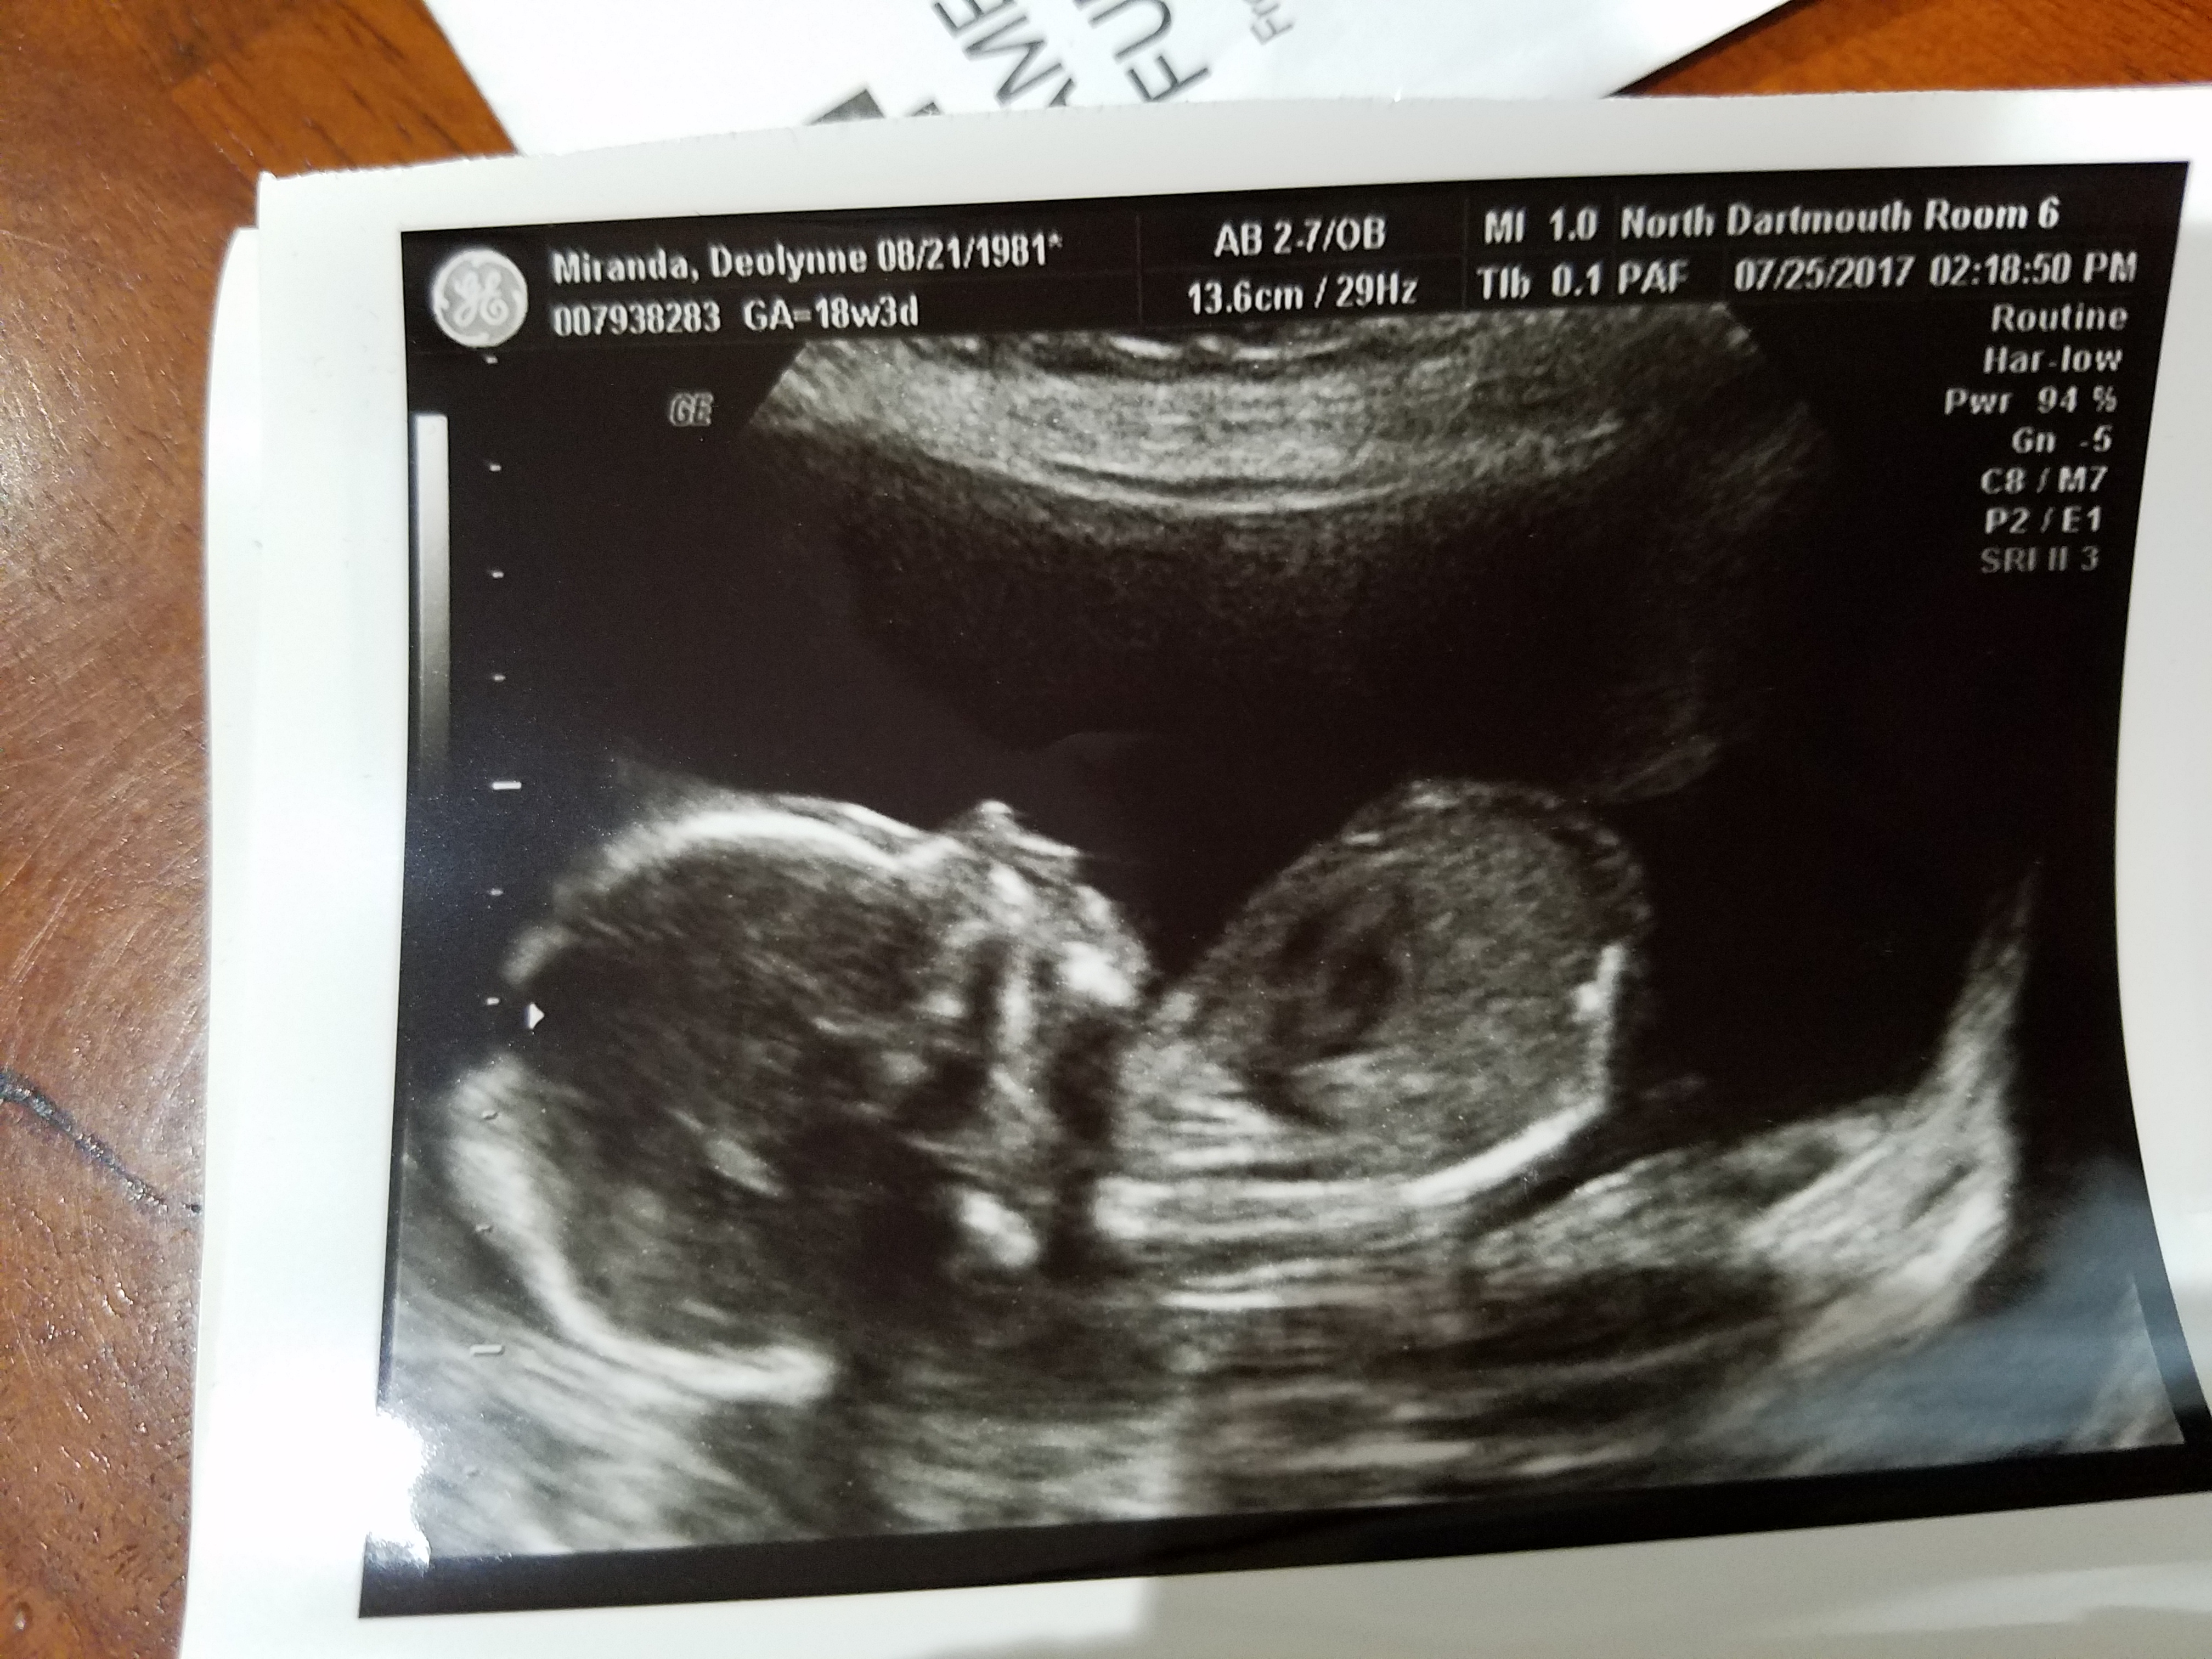

20170725_150313 Published August 25, 2017 at 4032 × 3024 in Lucky Bean In Utero « Previous Next » Like Loading...